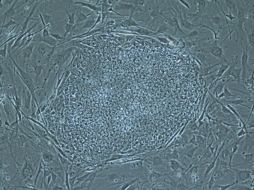

Tecnología Extraen células madre de embriones clonados 16 de mayo de 2013 - 01:03 hs Ciencia médica Células madre